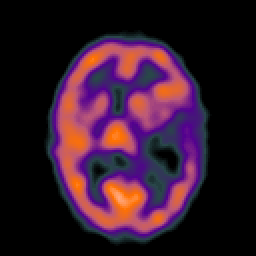

Metastatic bronchogenic carcinoma, overlay -- Slice #11

[Home][Help][Clinical] Slice 11